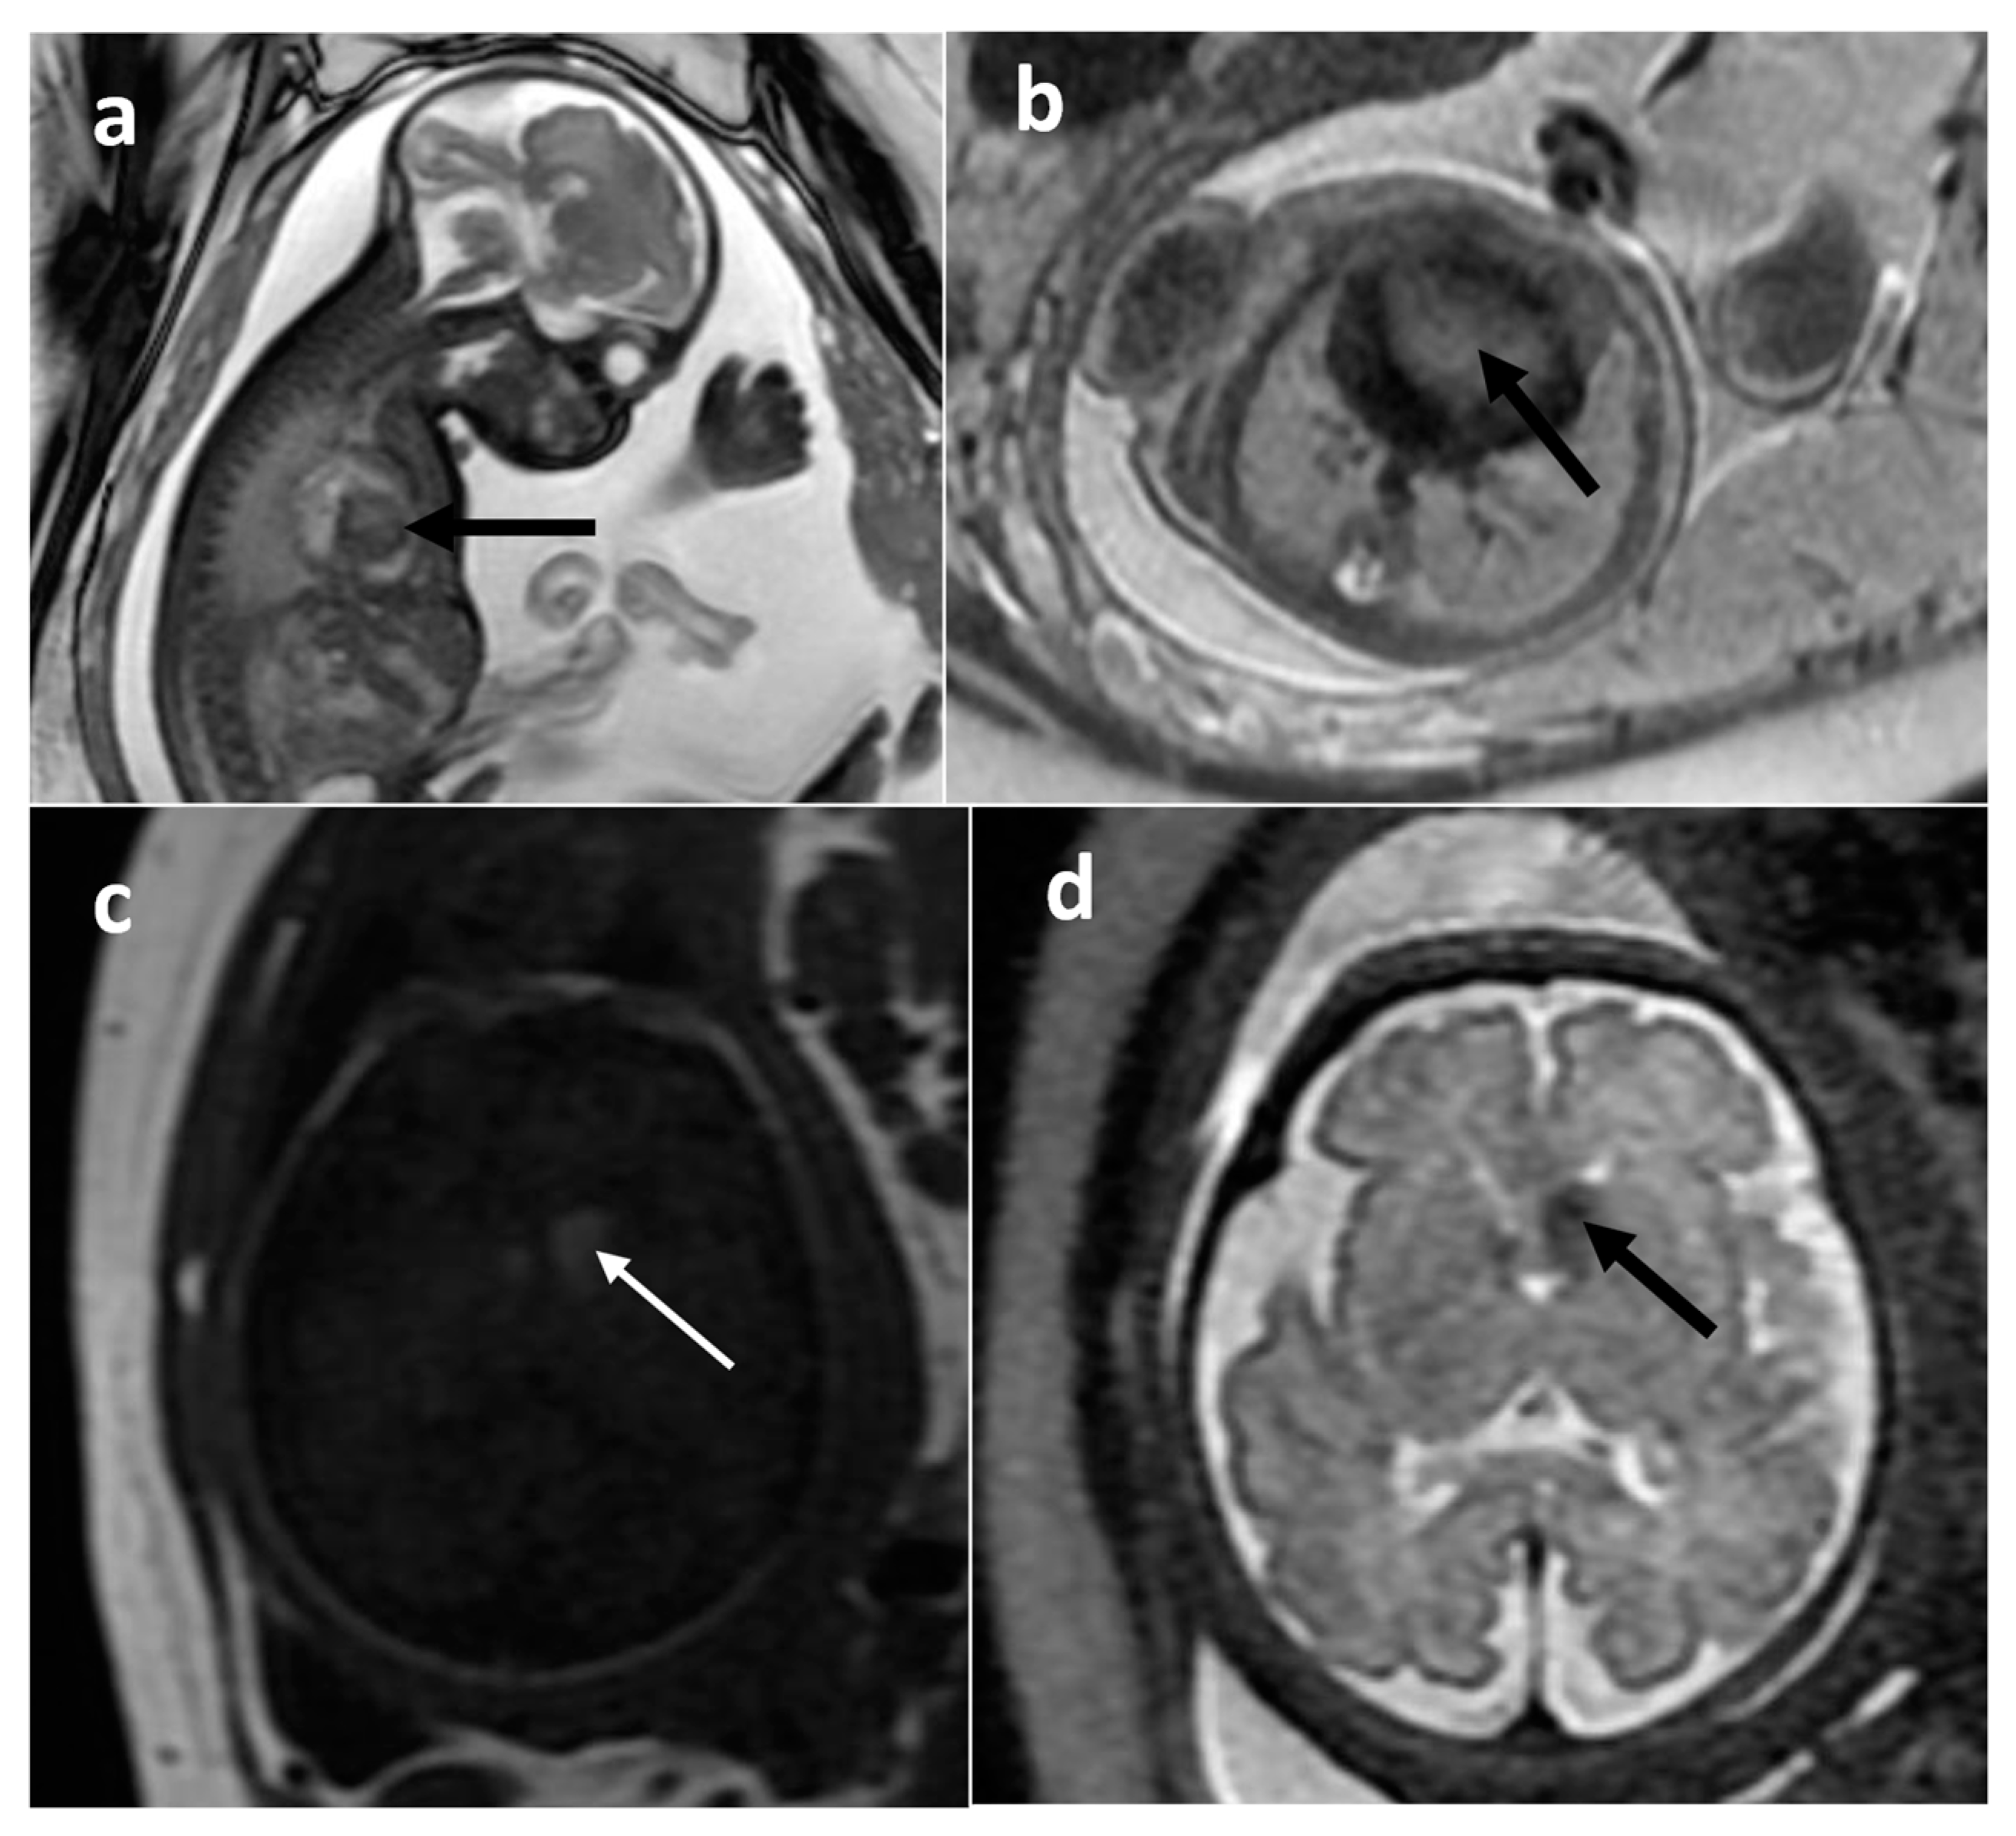

| Rhabdomyoma | heart | 22 | 5.08 [0.1–22] | no | Solid | No | N/A |

| Subependymal giant cell astrocytoma | foramen of Monro | 6 | 0.74 [0.59–0.89] | no | Solid | yes (2/2) | N/A |